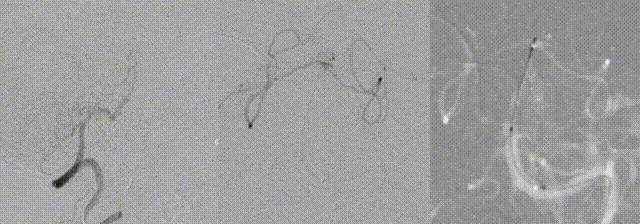

Switched to a 0.010-inch microwire, which successfully crossed the lesion and was advanced into the left superior cerebellar artery. Microcatheter angiography confirmed true lumen access. A Zenith Stent Retriever (4 mm × 20 mm) was deployed at the occlusion site.

- Zenith Stent Retriever advantages: Zenith Stent Retriever is compatible with 0.017-inch microcatheters. Tipless design enhances safety during distal thrombectomy. Full-length radiopacity facilitates precise assessment of lesion morphology. In this complex case, Zenith Stent Retriever enabled safe recanalization in a hypoplastic basilar artery without vascular injury.